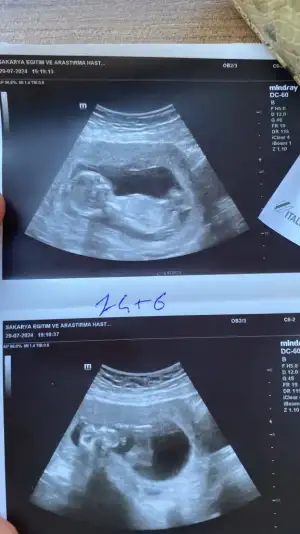

Kızlar öncelikle sağlıkla gelsin bebişlerimiz. Ben cinsiyetle alakalı bir şey sormak istiyorum. Baştan beri kız hissediyorum ilk bebegim ve 3 kez rüyamda kız gördüm. Hatta üçüncüsü çok netti suratını bile çizebilirim. Ama iki doktora gittim ikisi de erkek dedi 13-14. Haftada falandık sanırım. Şuan 16 olmak üzere. Acaba yanılma ihtimalleri var mı ben hala kız oldugunu hissediyorum rüyalardan dolayı kafam çok karışık.

Yanılma olabilir canım ben 12 haftada Medical park Keçiören hastanesinde çok iyi bi doktora gittim ve kesin erkek dediler ama ben hep kız hissediyorum hiç inanmadım 15.ve 17 haftada devlet hastanesine gittim ve bu bebek kız dediler kesinleşti kız olduğu Allah gönlüne göre versin inşallah

Merhaba Sakarya da mı yaşıyorsunuz